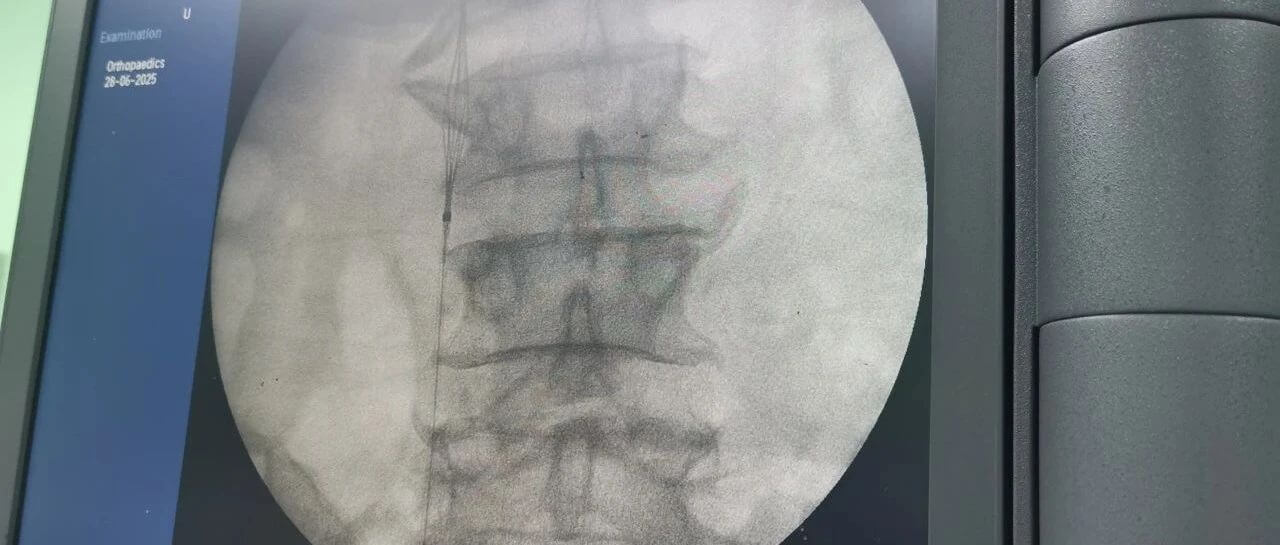

面對(duì)這一嚴(yán)峻挑戰(zhàn),羅軍副院長(zhǎng)團(tuán)隊(duì)果斷決策,先行實(shí)施“下腔靜脈濾器植入術(shù)”。手術(shù)團(tuán)隊(duì)?wèi){借精湛的技術(shù),在患者的下腔靜脈(人體最大的靜脈干)內(nèi)精準(zhǔn)放置了一個(gè)特殊的“濾網(wǎng)”裝置——腔靜脈濾器。它的核心作用就是充當(dāng)“血栓攔截網(wǎng)”:

攔截脫落的血栓:有效捕捉從下肢深靜脈脫落的血栓碎片,防止其隨血流進(jìn)入心臟和肺部。

預(yù)防致命肺栓塞:從根本上大幅降低患者在骨折手術(shù)期間及術(shù)后康復(fù)階段發(fā)生肺栓塞的風(fēng)險(xiǎn)。

保障后續(xù)手術(shù)安全:為接下來必須進(jìn)行的、耗時(shí)較長(zhǎng)的骨盆髖臼粉碎性骨折修復(fù)手術(shù)(尤其是利用3D打印技術(shù)進(jìn)行的精準(zhǔn)手術(shù))掃除了最大的安全隱患,提供了至關(guān)重要的手術(shù)安全保障期。